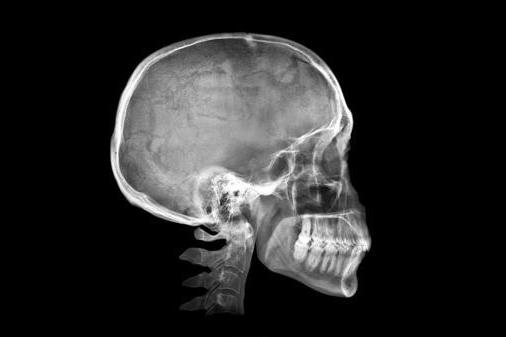

Исследователи говорят, что растет число людей, у которых появляются так называемые увеличенные наружные затылочные выпуклости у основании черепа.

Впервые о таких шипах заговорили в 1800-х годах, а теперь мы можем уже сами пальцами нащупать костяные шишки на черепе или увидеть их на лысых людях.

Они отсканировали более тысячи черепов, принадлежащих людям в возрасте от 18 до 86 лет.